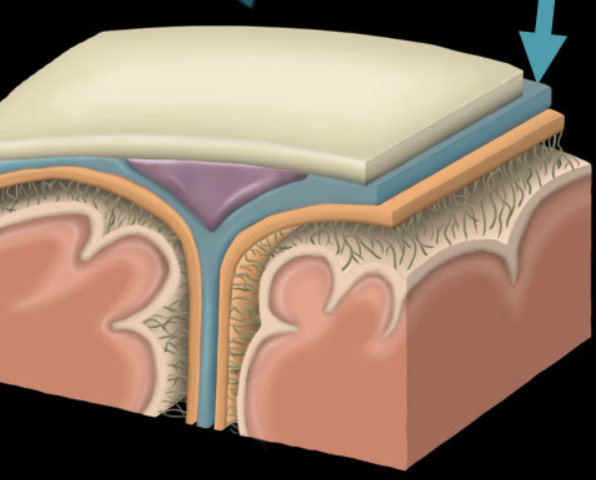

dura mater

arachnoid mater

Pia mater